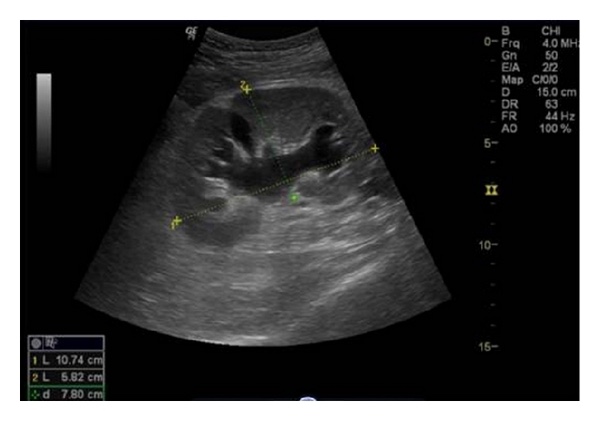

Ultrasound scans are non invasive and can take anywhere between 5-10 minutes to complete. The technician will take measurements and photos of the scans and will send these to the doctor to review.

There are serval things they can identify with a ultrasound scan. This includes things like blockages, kidney stones, dilation, blood flow and swelling.